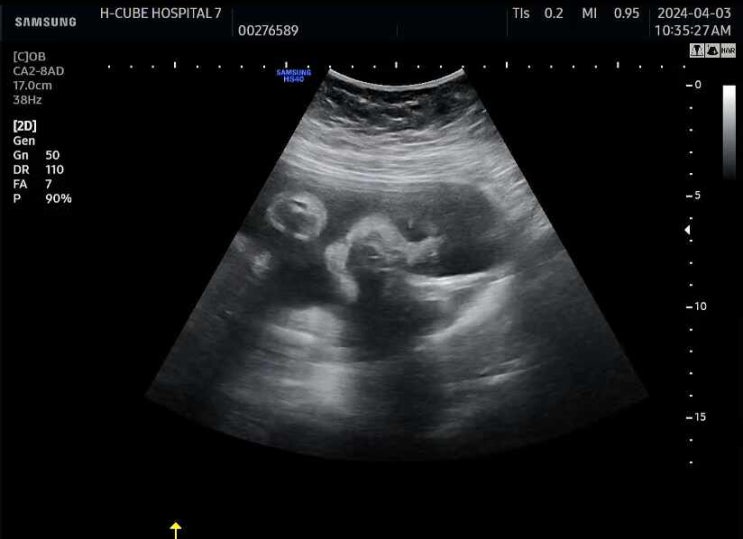

28w4d~28w6d - 자궁경부짧아짐/트랙토실/결국 대학병원으로 전원(상계백병원)/아시반/폐성숙주사/마그네슘

27w1d~27w3d - 포천공공산후조리원 실패 and 퇴원실패 후 27주된 하품하는 방울이